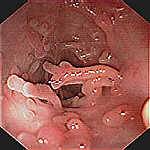

Leziunile precoce sunt granularitatea mucoasei, cu stergerea luciului si hiperemie. Apar ulterior ulceratii mici, superficiale, care cresc progresiv in dimensiuni. In fazele active pot fi acoperite de exudat muco-purulent sau hemoragic. In zonele de confluenta a ulceratiilor apar si denivelari - pseudopolipi inflamatori -zone de regenerare a mucoasei,cu tesut de granulatie, ce nu se malignizeaza.

STADIUL 3 (activitate severa ) |

Mucoasa hiperemica, edematiata, cu ulceratii multiple de dimensiuni variabile (2-4 mm), superficiale, neregulate, care sangereaza difuz la atingerea cu endoscopul, acoperite pe alocuri de exudate mucopurulente si hemoragice |

Stadiul 1 Stadiul 2 Stadiul 3

In faza de remisiune se repara epiteliul, cu formarea unei mucoase atrofice cu vascularizatie vizibila. Mai pot aparea pseudopolipi, dar nu exista sangerare si ulceratii. Exista forme cronice continue, cu fenomene de reparatie concomitente cu cele de distructie, ce duc la atrofia mucoasei rectale, cu aspect granular, hemoragii si ulcere. In formele tardive apar scurtari de colon si rect, ingustari de lumen colic si rectal, stergerea haustratiei colonice si o retractie sclerolipomatoasa. Toate acestea duc la microcolie si microrectie.

Remisiune-vase tortuoase, Remisiune- cicatrice liniare Pseudopolipi de regenerare

fara ramificatii